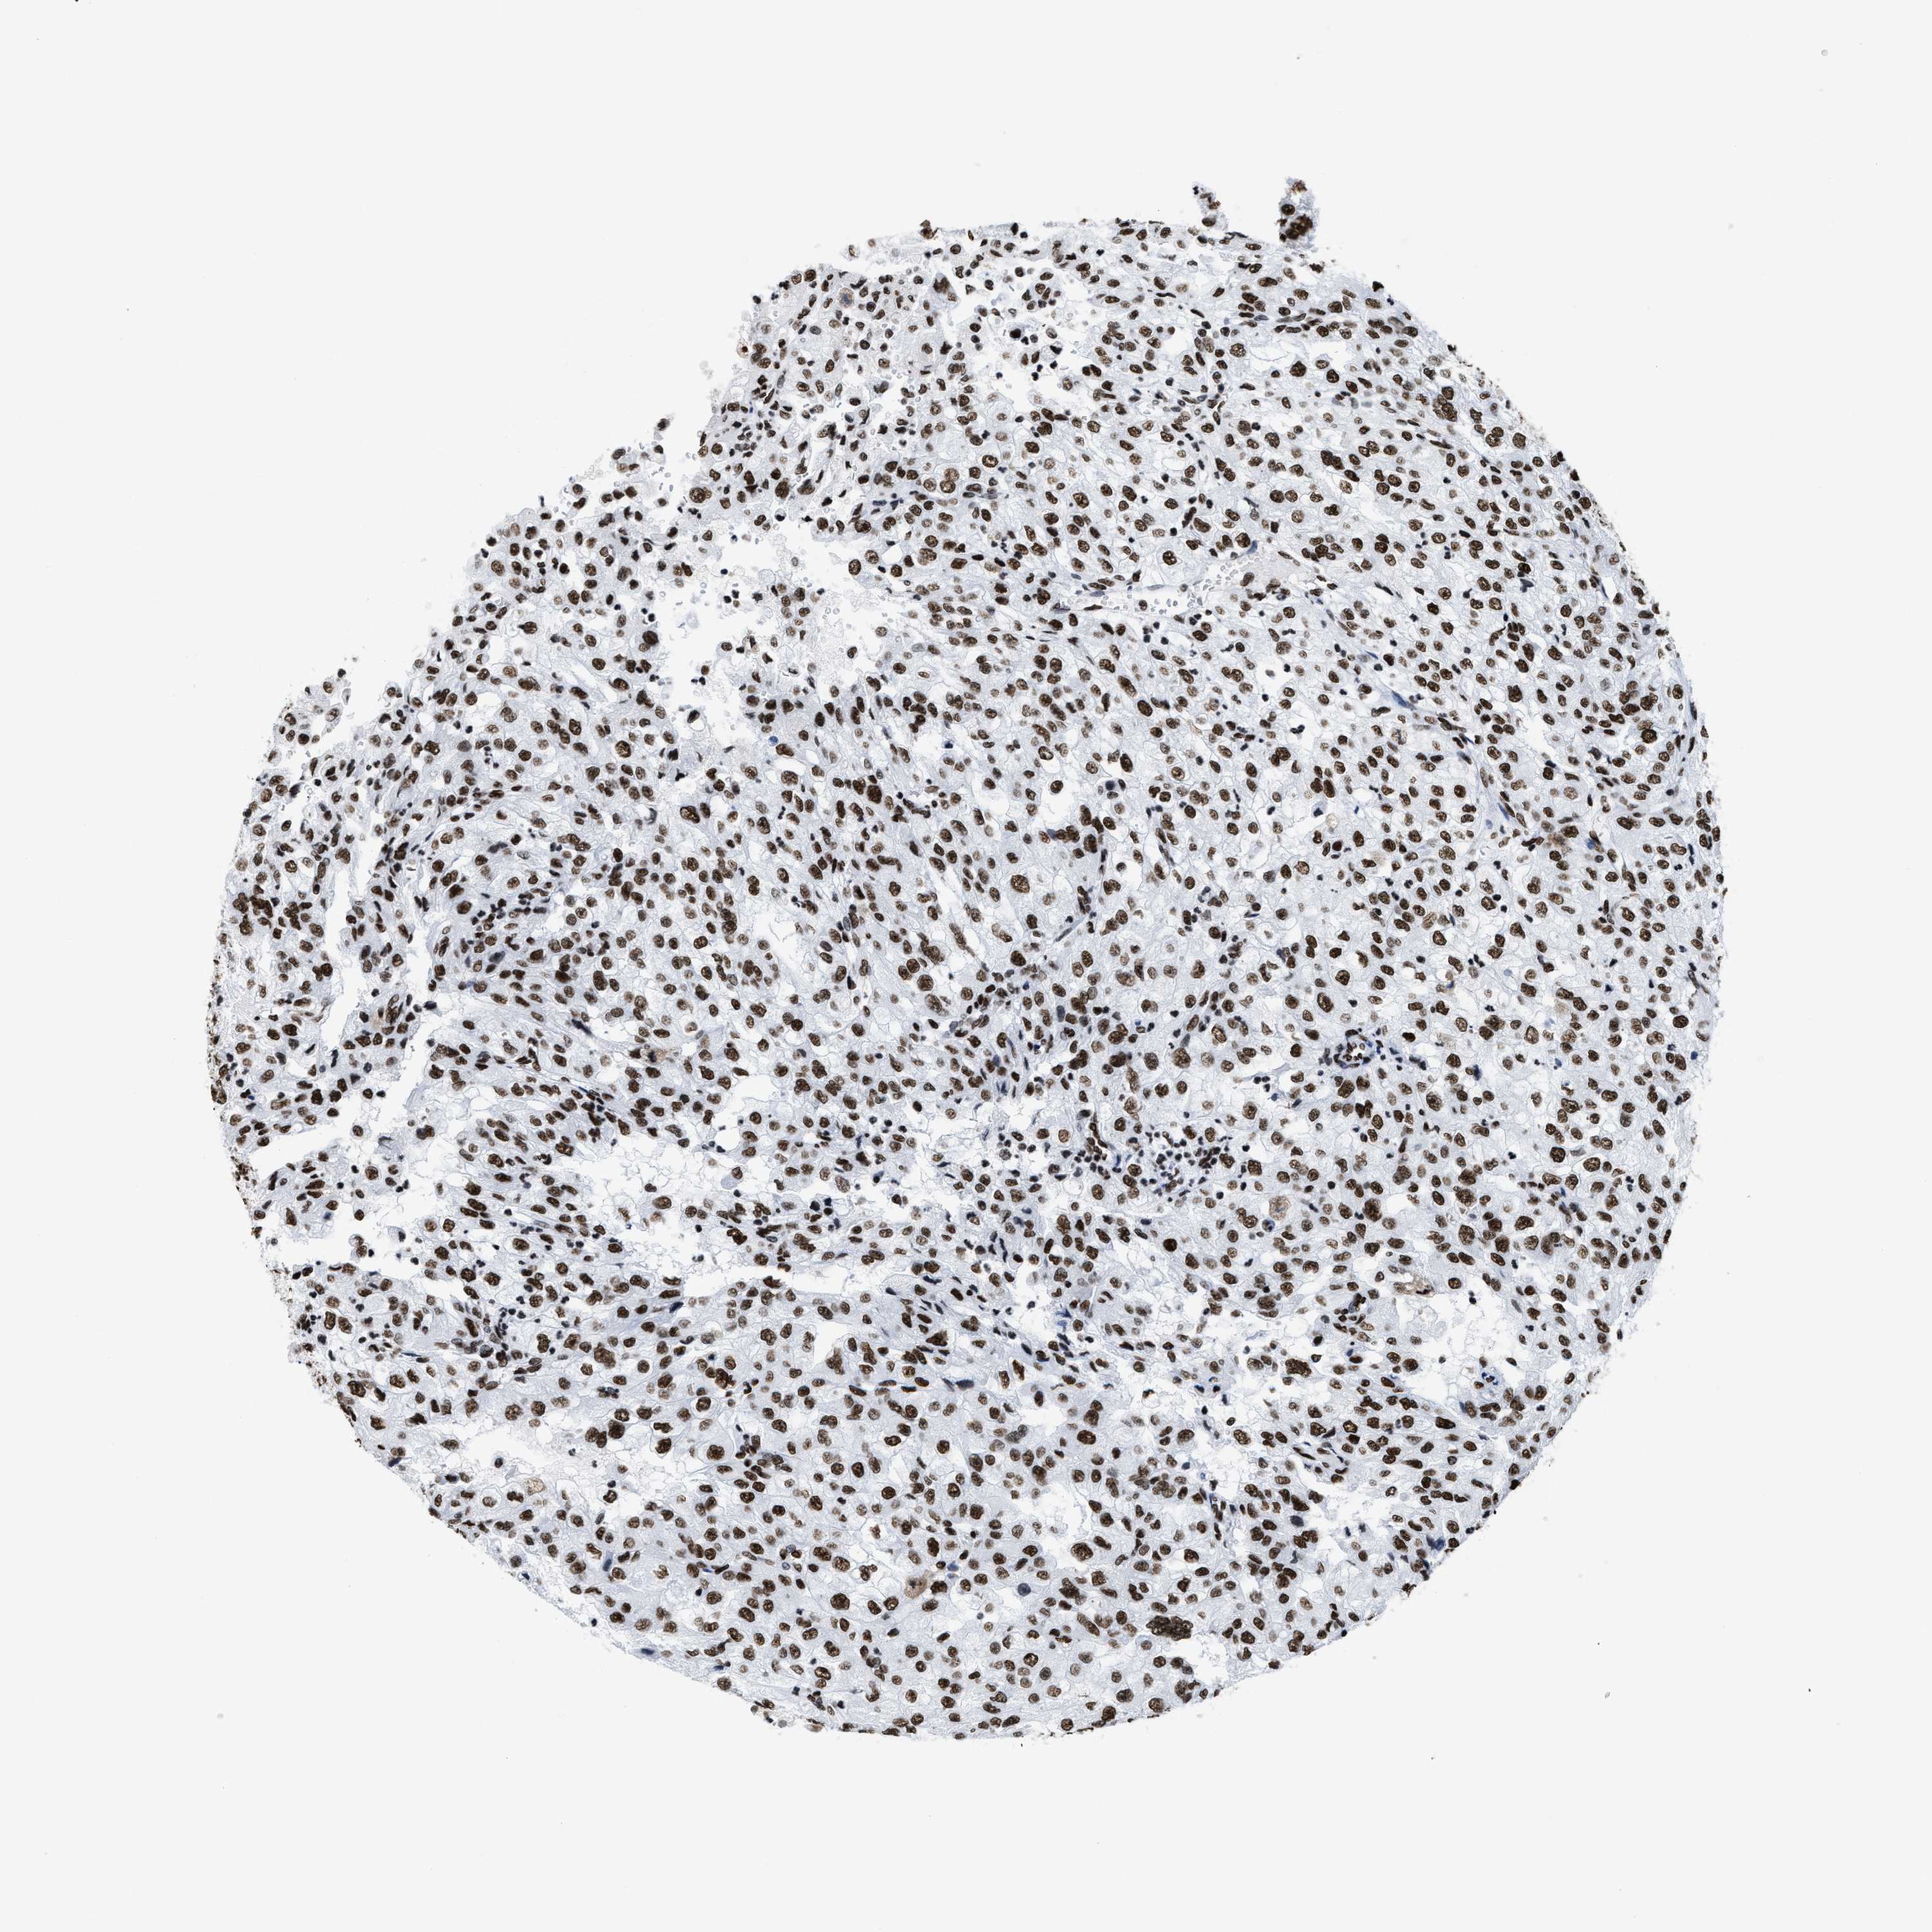

KIDNEY RENAL CLEAR CELL CARCINOMA (VALIDATION) - Interactive survival scatter ploti

The Survival Scatter plot shows the clinical status (i.e. dead or alive) for all individuals in the patient cohort, based on the same data that underlies the corresponding Kaplan-Meier plots. Patients that are alive at last time for follow-up are shown in blue and patients who have died during the study are shown in red.

The x-axis shows the expression levels (FPKM) of the investigated gene in the tumor tissue at the time of diagnosis. The y-axis shows the follow-up time after diagnosis (years). Both axes are complimented with kernel density curves demonstrating the data density over the axes. The top density plot shows the expression levels (FPKM) distribution among dead (red) and alive patients (blue). The right density plot shows the data density of the survived years of dead patients with high and low expression levels respectively, stratified using the cutoff indicated by the vertical dashed line through the Survival Scatter plot. This cutoff is automatically defined based on the FPKM cutoff that minimizes the p-score. The cutoff can be changed by dragging the vertical line or by entering a cutoff value in the square labeled "Current cut-off".

Under the Survival Scatter plot the p-score landscape (black curve; left axis) is shown together with dead median separation (red curve; right axis). Dead median separation is the difference in median mRNA expression between patients who have died with high and low expression, respectively. It is calculated as follows: median FPKM expression of dead patients with high expression - median FPKM expression of dead patients with low expression. This is intended to aid the user in visually exploring custom cutoffs and the associated p-scores and dead median separation.

Individual patient data is displayed and can be filtered by clicking on one or more of the category buttons on the top of the page. Categories describing expression level and patient information include: high, low, alive, dead, female, male and tumor stages. The scale of the x-axis can be toggled between linear and log-scale by clicking on the "x log" button. Mouse-over function shows TCGA ID, patient information and mRNA expression (FPKM) for each patient.

& Survival analysisi

Kaplan-Meier plots summarize results from analysis of correlation between mRNA expression level and patient survival. Patients were divided based on level of expression into one of the two groups "low" (under cut off) or "high" (over cut off). X-axis shows time for survival (years) and y-axis shows the probability of survival, where 1.0 corresponds to 100 percent.

SMARCC2 is not prognostic in Kidney Renal Clear Cell Carcinoma (validation)

Best expression cut offi

Based on the FPKM value of each gene, patients were classified into two groups and association between prognosis (survival) and gene expression (FPKM) was examined. The best expression cut-off refers the FPKM value that yields maximal difference with regard to survival between the two groups at the lowest log-rank P-value. Best expression cut-off was selected based on survival analysis .

When clicking on this number, the vertical dashed line indicating cut-off, the interactive survival plot, and the Kaplan-Meier curve will be adjusted to show results based on the best expression cut-off.

: 44.04

P scorei

Log-rank P value for Kaplan-Meier plot showing results from analysis of correlation between mRNA expression level and patient survival.

N/A

TCGA RNA samplesi

RNA-seq data is reported as average FPKM (number Fragments Per Kilobase of exon per Million reads), generated by the The Cancer Genome Atlas (TCGA) .

Normal distribution across the dataset is visualized with box plots, shown as median and 25th and 75th percentiles. Points are displayed as outliers if they are above or below 1.5 times the interquartile range. FPKM values of the individual samples are presented next to the box plot.

Average pTPM 43.8

Number of samples 100